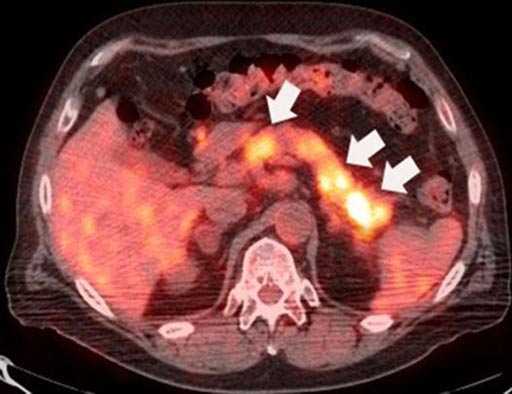

ПЭТ — позитронно-эмиссионная томография — идеальный инструмент для поиска метастазов. В организм пациента вводят безопасное радиоактивное соединение, которое накапливается в раковых клетках. Из-за этого они становятся видны на специальных снимках. Иногда ПЭТ выполняют вместе с КТ, чтобы лучше понять, где находятся метастазы.

Позитронно-эмиссионная томография

Существуют более дорогие диагностические методики, например, позитронно-эмиссионная томография, но выполнение её как первого метода исследования нецелесообразно в связи с высокой стоимостью.